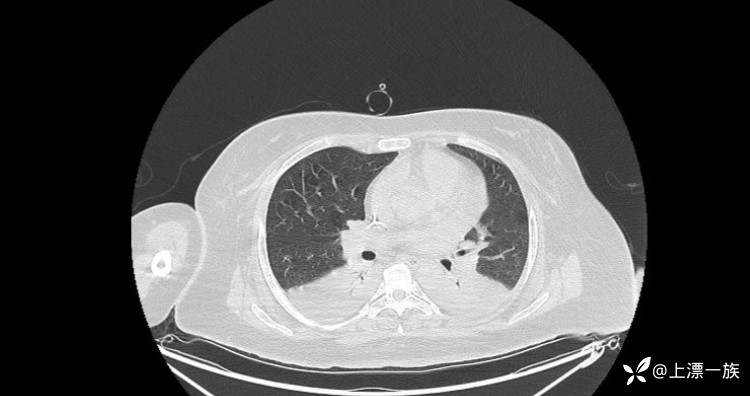

复查CT胸部

开始减少补液,因胸水开始出现了,开始拉水。